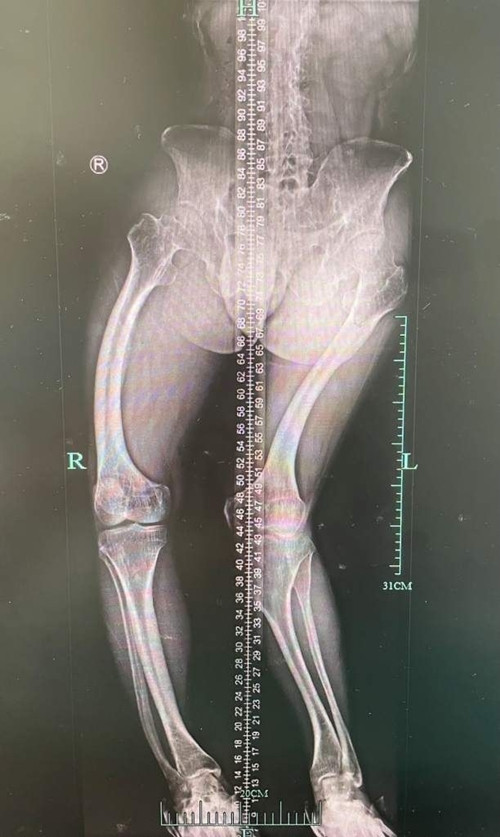

| Phim chụp xương sống của anh Lý Vũ Dũng. |